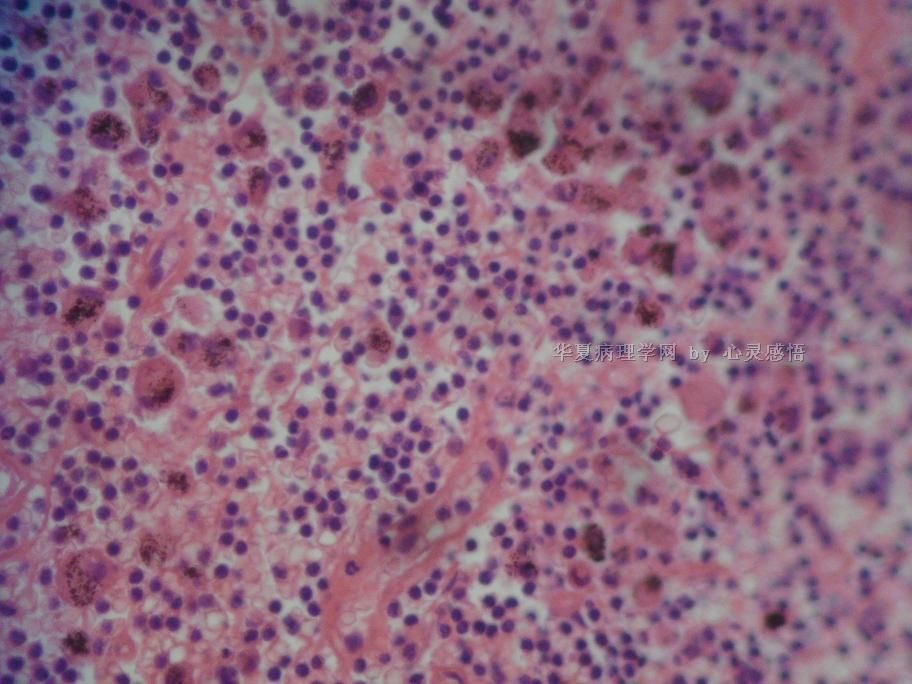

• 食道癌,淋巴结有没有转移,谢谢。图3

图3

1-6图是鳞癌。7-22图片无癌。

淋巴结没有转移

本帖最后由 于 2010-11-17 20:19:00 编辑  图14,19有转移

请教楼主;图片19是淋巴结吗?如果是应该是有癌转移!

没有转移,食道旁的淋巴结和肺旁的淋巴结相似,含有吞噬细胞。